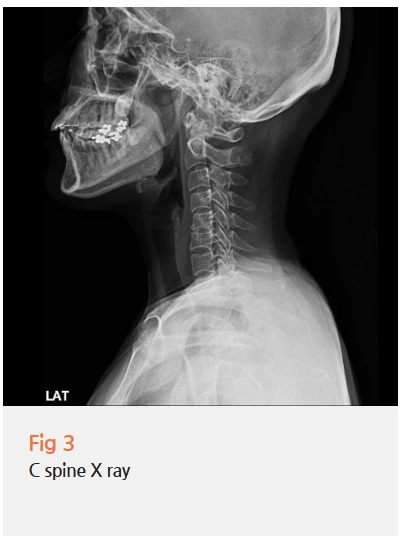

그 다음은 경추 X-ray였어요.

사실 눈이 떨리는데 왜 목 검사를 하냐고 의아해하시는 분들이 많아요.

이 환자분도 처음엔 눈이 문제인데 왜 목을 보냐는 표정을 지으셨거든요.

그런데 경추와 눈 떨림의 연관성은 생각보다 명확한 의학적 근거가 있어요.

목 주변 근육과 신경이 과도하게 긴장 상태에 놓이면, 교감신경 긴장도가 함께 높아져요.

교감신경이 과활성화되면 안면부 신경과 근육도 영향을 받게 되는데,

이때 눈둘레근 같은 작고 예민한 근육이 가장 먼저 반응하는 경우가 많아요.

그게 눈 밑 떨림으로 나타나는 거예요.

특히 과거에 목 디스크 치료 이력이 있거나,

평소 목이 자주 뻐근하고 두통이 함께 동반된다면 이 가능성을 반드시 고려해야 해요.

이 환자분의 경우, 경추 X-ray에서 목 정렬 이상 소견이 확인되었고 과거 목 디스크 치료 이력도 있으셨어요.

임상 양상과 검사 결과를 종합했을 때, 경추부 긴장과 자율신경 이상이 눈 떨림의 핵심 원인이라는 판단이 섰습니다.